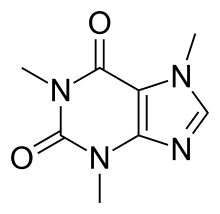

Chemistry

Pure anhydrous caffeine is a bitter-tasting, white, odorless powder with a melting point of 235–238 °C.[11][12] Caffeine is moderately soluble in water at room temperature (2 g/100 mL), but very soluble in boiling water (66 g/100 mL).[193] It is also moderately soluble in ethanol (1.5 g/100 mL).[193] It is weakly basic (pKa of conjugate acid = ~0.6) requiring strong acid to protonate it.[194] Caffeine does not contain any stereogenic centers[195] and hence is classified as an achiral molecule.[196]

The xanthine core of caffeine contains two fused rings, a pyrimidinedione and imidazole. The pyrimidinedione in turn contains two amide functional groups that exist predominantly in a zwitterionic resonance the location from which the nitrogen atoms are double bonded to their adjacent amide carbons atoms. Hence all six of the atoms within the pyrimidinedione ring system are sp2 hybridized and planar. The imidazole ring also has a resonance. Therefore, the fused 5,6 ring core of caffeine contains a total of ten pi electrons and hence according to Hückel's rule is aromatic.[197]